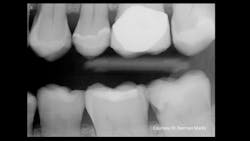

Figure 2: Obviously, the radiograph in Figure 1 did not show the major carious lesion.

Recently, one of our practicing dentist team members who donates significant time to Clinicians Report Foundation and Practical Clinical Courses sent me a clinical example that frustrated both of us (figures 1 and 2). As you observe Figure 1, you will immediately see a lesion on the mandibular second molar and—perhaps—a small lesion on the maxillary first premolar. But do you see the lesion on the maxillary second molar? As you observe Figure 2, you are shocked to see the depth of the MO lesion that was not visible on the radiograph.